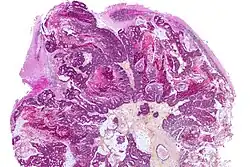

Micrograph showing a colorectal carcinoma metastasis to the cerebellum. HPS stain.